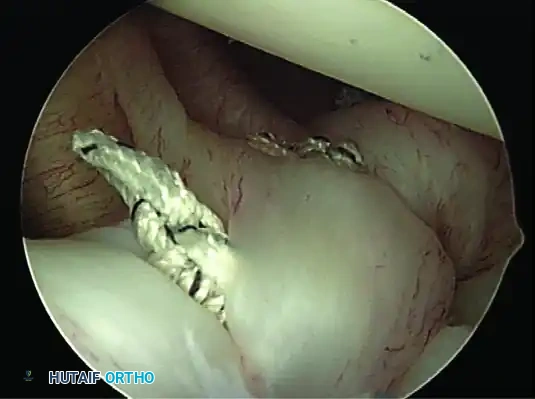

4. Suture Passing and Superior Advancement

To eliminate the drive-through sign and restore physiological tension, the capsule must be shifted superiorly and laterally.

- Retrieve the most inferior suture limb out of the posteroinferior cannula using a suture grasper.

- Use a Spectrum suture passer through the anterior cannula to take a substantial (1 cm) bite of the capsule and labrum inferior to the anchor site.

C, A 1-cm capsular bite taken with Spectrum suture passed distal to anchor.

- Shuttle the PDS relay suture out the posterior cannula, load the anchor suture, and pull it through the capsulolabral tissue.

- Retrieve the corresponding suture limb and tie a secure, low-profile sliding knot (e.g., SMC or Weston knot) backed up by alternating half-hitches.

5. Recreating the Anterior Bumper

Proceed superiorly, placing the second and third double-loaded anchors. Firmly secure the sutures, compressing the capsuloligamentous complex to the abraded bone surface. This "loop and knot fixation" rolls the tissue up onto the glenoid face, recreating a robust anterior soft-tissue bumper.

D, Knots tied re-creating soft tissue bumper.